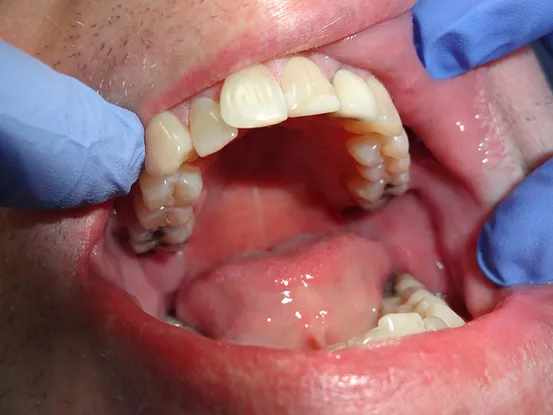

Case 6

77 year old male with 30 plus year old failing 4 unit bridge. Treatment was delayed for years due to high dental anxiety. Patient was reassured and 6 units of porcelain fused to metal crowns resulting in much improved smile in less than 2 weeks.